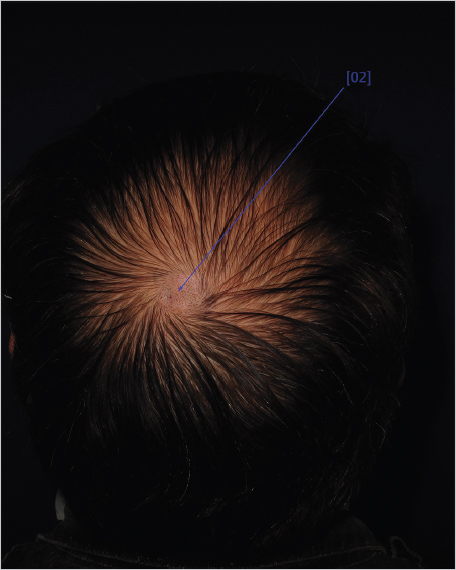

The procedure is performed in two steps 3 days a part. On the first day, the patient visits the doctor’s office and a specific area of the scalp is selected. A flip-card containing a 1.8cm2 hole provided by the company is put onto the selected area. Using an electric razor, hairs in this 1.8cm2 area are clipped (Fig. 6.1). The patient is then asked to return to the office 3 days later for the second step of the procedure.1,2,3

Fig. 6.1 TrichoScan method. Figure shows a patient in whom the selected area has already been clipped and marked with red ink. This patient was part of a treatment protocol and the vertex area was chosen because of the higher number of thinning hairs compared to other area. (The image is provided courtesy of Dr. Priscila Kakizaki, São Paulo, Brazil.)